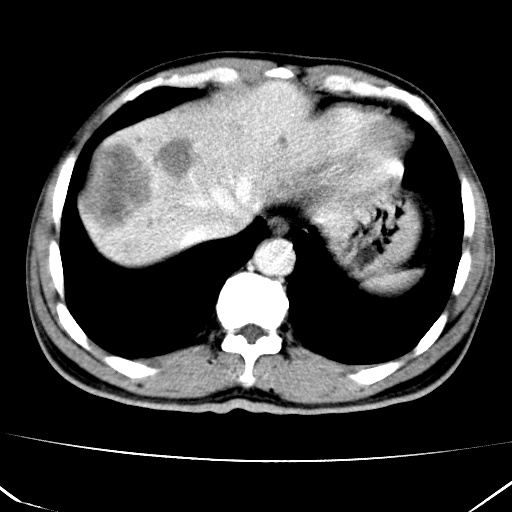

标题: CT17975:请求会诊。男、57岁。上腹部胀痛2天。临床诊断:糜 [打印本页]

标题: CT17975:请求会诊。男、57岁。上腹部胀痛2天。临床诊断:糜

考虑---胃癌肝脏转移可能---建议---胃镜

肝脏多发类圆形低密度影,考虑肝脏转移瘤,肝胃韧带一淋巴结肿大,原发?胃癌?

考虑胃癌肝脏转移可能性大。

考虑胃癌并肝脏及腹膜后淋巴结转移;不排除淋巴瘤。

肝内转移瘤,腹腔及腹膜后淋巴结转移。